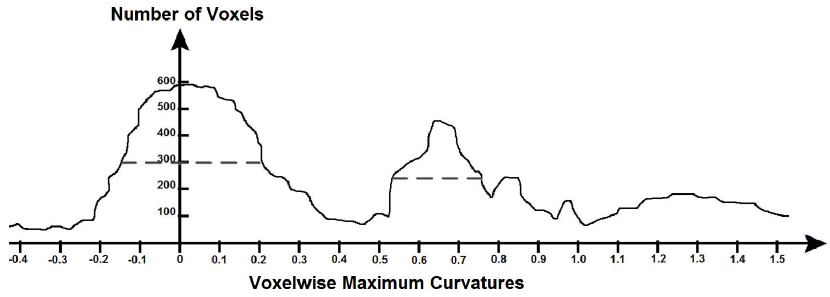

The surface of each segmented cardiac structure got voxelized to identify its surface voxels. In each surface voxel, the magnitude and the direction of the maximum curvature and the outward normal got calculated. Then, a histogram of the magnitudes of the maximum curvatures got collected across all the surface voxels. Figure 10 shows this histogram for a cardiac surface. In this histogram, the full width at half maximum (FWHM) of the lower peak defined the typical curvatures of the myocardium and the FWHM of the upper peak defined the typical curvatures of the cardiac vessels. This, as shown in Figure 9, was because the myocardium had a larger diameter and thus a lower curvature than the vessels. Every sample whose patch contained at least one surface voxel was designated to be a surface sample. Among all the surface voxels of every surface sample, median of magnitudes of maximum curvatures, median of directions of maximum curvatures, and median of outward normals got calculated to define the magnitude of maximum curvature, the direction of maximum curvature, and the outward normal of the surface sample, respectively. If the magnitude of maximum curvature of a surface sample was among the typical curvatures of the myocardium/cardiac vessels, then the sample was a myocardium/vessel sample.